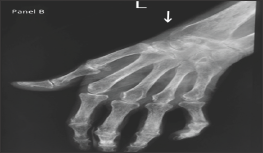

Figure 1: Flexion of the metacarpophalangeal joint and extension of the interphalangeal joint of the thumb (Z-deformity) and flexion deformity of the 2nd to 5th proximal interphalangeal joints.

A 58-year old lady, with history suggestive of inflammatory joint pains since 17 years and very poor compliance to treatment, presented with chronic diarrhea since 2 months. On examination, patient had Z-shaped thumb deformity and flexion deformity of her fingers which are typically seen in rheumatoid arthritis. On evaluation, patients' complete blood counts were Hemoglobin (Hb-7.3gm/dL, Total Leucocyte Count (TLC)- 11.2x 109/L with differential leucocyte count-polymorphs 70%, lymphocytes 22%, eosinophils 4% and basophil 4%, platelet Count 236 x 103, ESR was 55 mm/hr and peripheral smear showed microcytic to normocytic RBCs and hypochromasia. Biochemistry investigations revealed serum sodium 135mmol/L, serum potassium 3.5mmol/dL, blood urea nitrogen- 48mg/dL, creatinine 2.1mg/dL, and Total protein- 4.8 mg/dL, serum albumin 1.6 with albumin: globulin ratio 1: 3.8, Serum calcium- 8.8mg/dL. X ray of the involved joints showed peri-articular osteopenia with symmetrical narrowing of the joint spaces. 24-hour urinary protein showed massive proteinuria (3.3gm/24 hrs). Stool workup was negative for microorganisms and fat globules (Figures 2 & 3). Upper GI endoscopy was done which revealed Amyloid deposits that were positive for Serum Amyloid Associated protein. As patient developed leucopenia secondary to methotrexate 2 months prior to the current admission, it was deferred and she was started on Lefunomide after which her proteinuria and diarrhea gradually improved.

Figure 2: Periarticular osteopenia and symmetrical narrowing of the joint spaces of metacarpophalangeal and proximal interphalangeal joints.